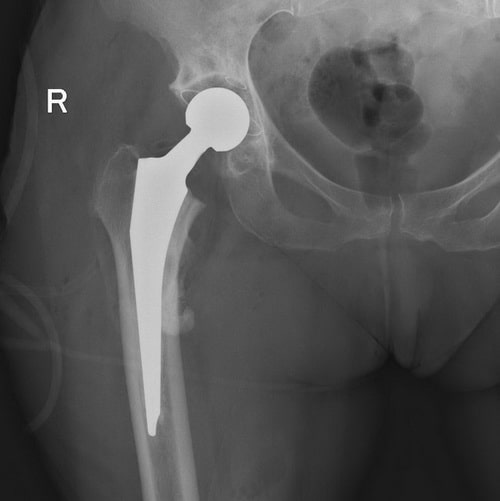

Диагностика ТБС рентгеном и асептический некроз: особенности лечения

Раздел: Снимки-откровения